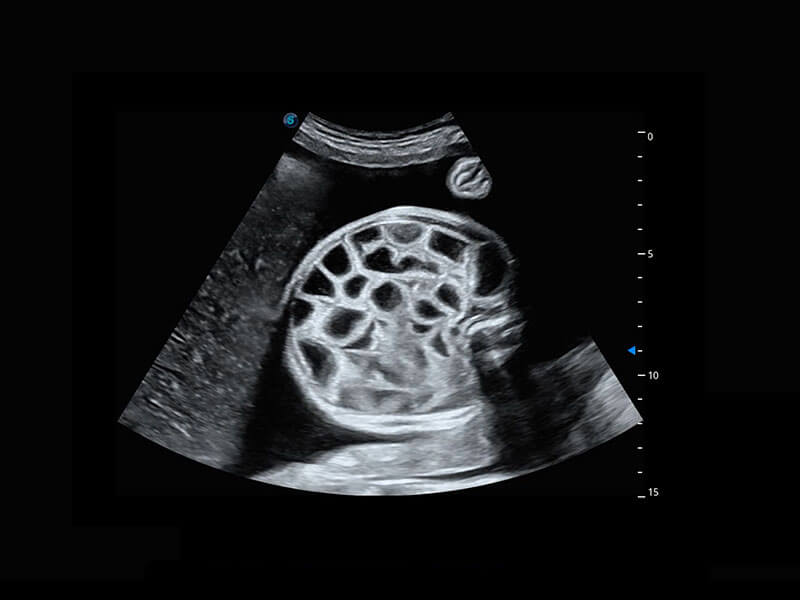

P60提供简单易学易用的高端诊断工具,为您中晚孕筛查提供快速清晰的解剖信息。

1 OFD(HC): 87.03 mm

HC: 251.00 mm

GA: 27w 1d

HC/AC: 96.13 %

2 BPD: 70.56 mm

GA: 28 w 2d

S-Fetus(acq.)

&

S-Fetus(meas.)

S-Fetus能够助您在实时扫查过程中自动识别标准切面、自动测量并录入报告。一个按键,即可快速、高效地获取胎儿生理指标,简化您的产科检查操作。